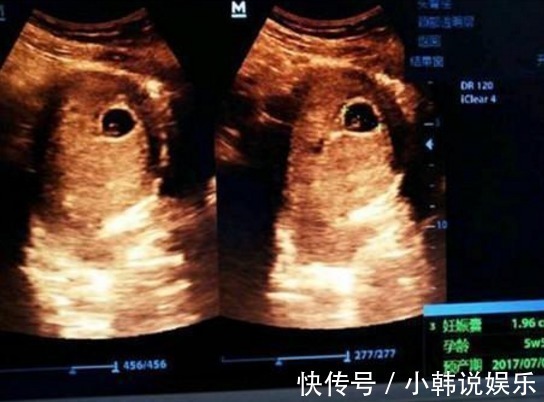

好多人说各种判断不准或者怎样,个人认为:根据个人体质不同会有区别,但是因为怀男孩女孩所产生的不同种激素,会导致每个人反应不同才是更大原因,孕检时,B超单上的3个“数据”,真幸运,可能怀了个“小棉袄”!(1)宝宝的股骨长:妈妈在怀孕的六个月左右的时间内,宝宝的各个器官就已经发育得比较成熟了,因此宝妈在做四维彩超的时候。

B超检查既能对胎盘定位、羊水测量,又能对单胎多胎、胎儿发育情况及有否畸形和葡萄胎等作出早期诊断。就可以看到宝宝的各个器官,当准妈妈拿到B超单时,可以观察宝宝的股骨长,如果宝宝的股骨长比较大的话,那么肚子中怀的很有可能就是一位男宝宝了,相反的话,如果不够长,没有那么大比较偏小的话,那么很有可能就怀的是个“小棉袄”,

(3)双顶径:她准妈妈拿到B超单上可以反复观察双流这项数据,就是指的是宝宝头部的宽度,如果准妈妈发现双顶径的数据减去股骨长的数据大于二的话,那么多的小王子的可能性就比较大一些,因为小王子的头部要比小棉袄主的头部大一些,当然这些数据也没有什么百分之百的确定性,只不过是过来人的一些经验总结。孕中期的B超检查,可以面部、神经系统、消化系统、泌尿系统等有无畸形。